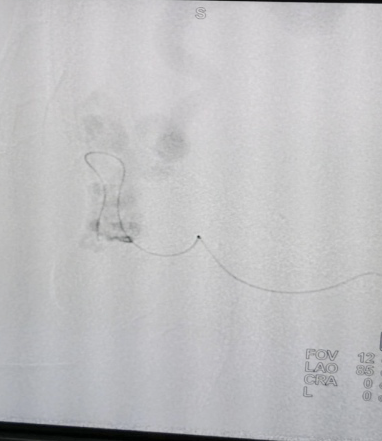

▲三维重建

▲术中情况